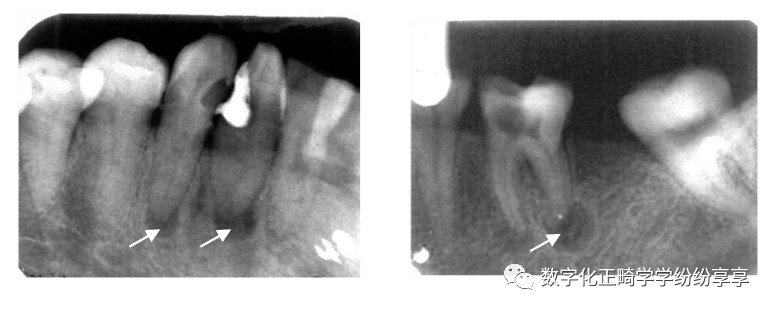

牙槽骨水平型吸收

曲面断层片怎么看正畸【曲面断层片(全景片)】如何解读和查看:牙周?牙体?牙髓?关节?_https://www.jmylbn.com_新闻资讯_第13张

多数牙或全口牙槽骨从嵴顶呈水平方向向根尖高度减低,吸收程度较均匀,早期表现牙槽嵴顶骨硬板模糊,继而前牙区牙槽嵴顶由尖变平,后牙区牙槽嵴顶由梯形变凹陷,边缘模糊粗糙呈虫蚀样;随疾病进一步发展,牙槽嵴逐渐向根尖方向吸收。

牙槽骨垂直型吸收

曲面断层片怎么看正畸【曲面断层片(全景片)】如何解读和查看:牙周?牙体?牙髓?关节?_https://www.jmylbn.com_新闻资讯_第14张

表现为局部牙槽骨或牙槽间隔的一侧,沿牙体长轴方向向根端吸收,病变早期造成牙槽骨壁吸收,骨硬板消失,牙周间隙增宽;随病变加重,牙槽骨垂直吸收明显,呈楔形,若同一牙齿近远中均有垂直吸收,牙槽骨可见弧形吸收(吸收区域包绕两个及以上牙面)。

牙槽骨混合型吸收

曲面断层片怎么看正畸【曲面断层片(全景片)】如何解读和查看:牙周?牙体?牙髓?关节?_https://www.jmylbn.com_新闻资讯_第15张

牙槽骨在水平吸收的基础上,同时伴有个别牙或多数牙的牙槽骨垂直吸收。多见于牙周炎晚期。